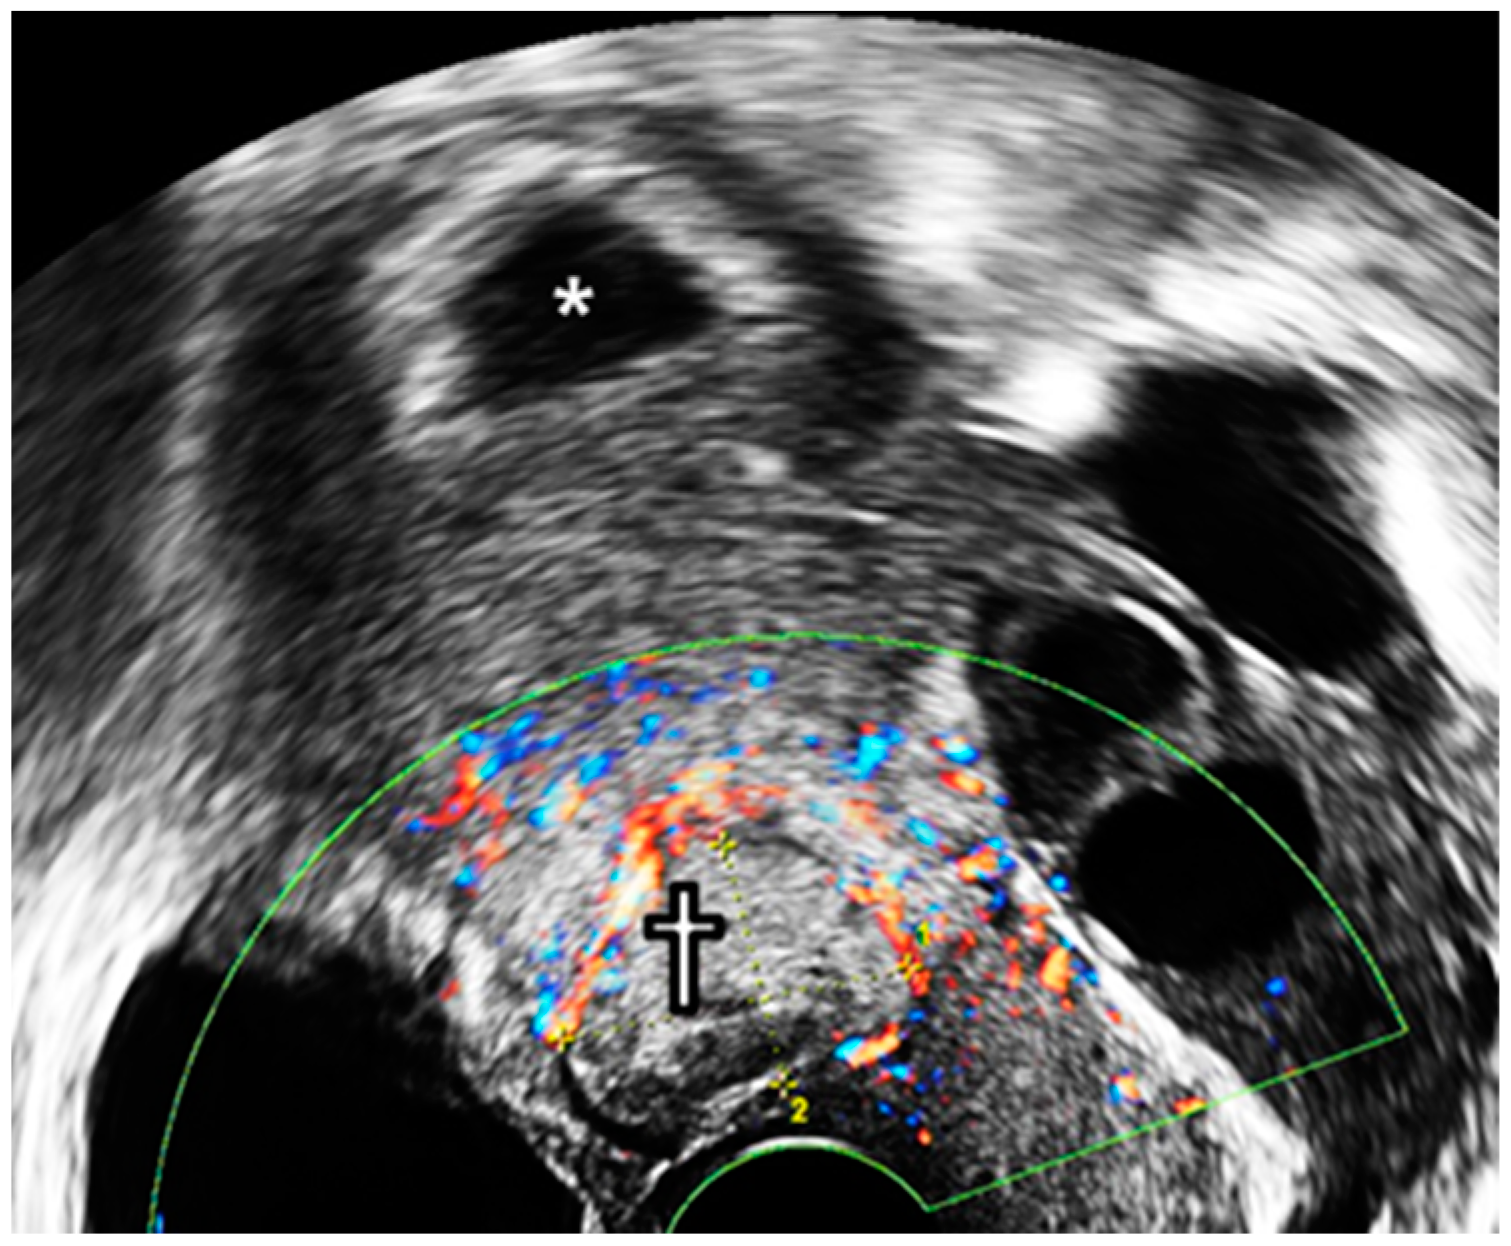

A 36-year-old woman (gravida 2, para 1) was transferred from a local hospital because of a cesarean ectopic pregnancy with IUP. The patient underwent in vitro fertilization-embryo transfer (IVF-ET) using two ova. Two years ago, she delivered a baby via a lower segment cesarean section. Ultrasonography at 6+1 gestational weeks (GW) revealed two gestational sacs; one in the uterine fundus and the other in the anterior uterine isthmus (Figure 1a,b). Both had fetal cardiac activity, and the mother had no vaginal bleeding or abdominal pain.

Figure 1. Initial examination. (a) Initial transvaginal ultrasound examination at 6+1 GW. *—intrauterine gestational sac; †—CSP. (b) Description of sagittal plane.